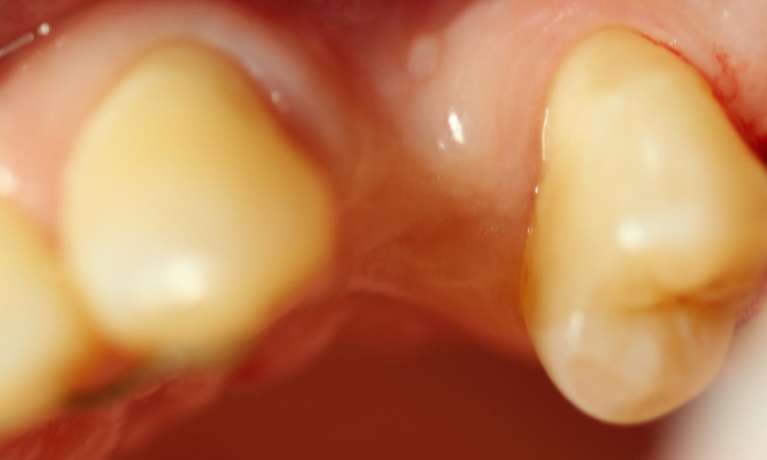

This case showcases the successful outcome of a gum graft procedure performed around an existing dental implant. Initially, the patient experienced gum recession around their implant, which can sometimes expose the implant's margin or simply lead to an uneven gum line.